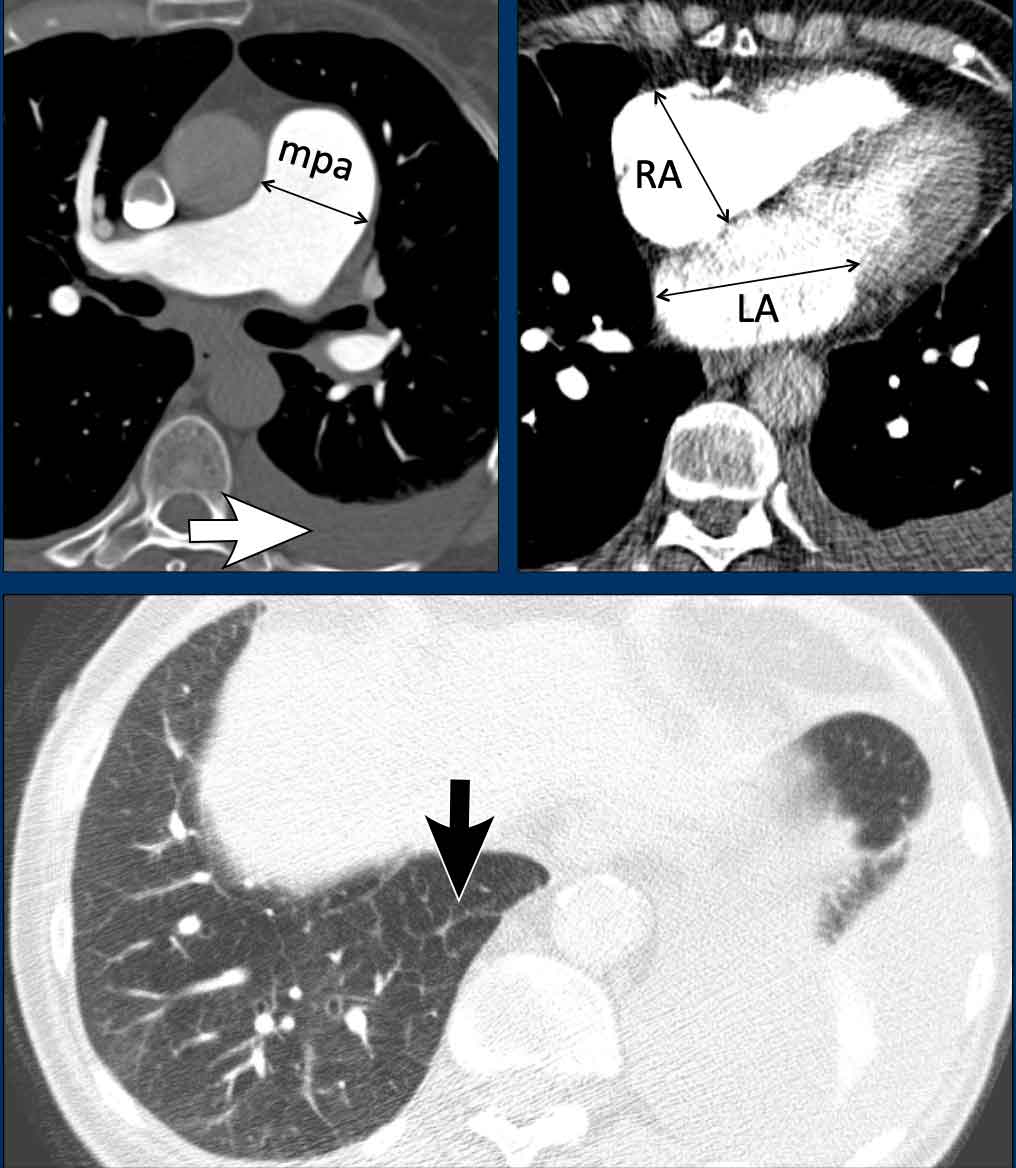

These images are of a young female with idiopathic PAH.

Imaging findings

1. Mild dilatation of the main pulmonary artery

2. Mild dilatation of the right ventricle.

3. Mild wall thickening of the right ventricle outflow tract (arrow).

The left atrium has a normal size.

4. Normal lung parenchyma.

Images

In this patient with left heart disease the findings are:

1. Dilatation of the main pulmonary artery.

2. Dilatation of the right atrium and mild thickening of the myocardium of the right ventricle.

3. Dilatation of the left atrium

4. Pleural fluid (white arrow).

5. Smooth interlobular thickening (black arrow).